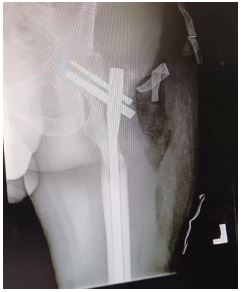

Case 6

A 38-year-old male presented with a Gustilo-Anderson Grade IIIB open comminuted fracture of the left femur after a gunshot injury. The wound underwent a washout and this was followed up by ORIF using a Trochanteric Fixation Nail (TFN) (Figure 6). This was followed by primary closure of the wound and application of Vacuum-Assisted Closure (VAC) dressing. His post-operative course was uneventful and the wound healed after 18 days. The patient was allowed to mobilise with partial weight-bearing for 3 weeks followed by full weight-bearing as tolerated.

Images are Not Display Check it

Figure 6: Anteroposterior view radiograph of the left leg showing the trochanteric fixation nail fixation.